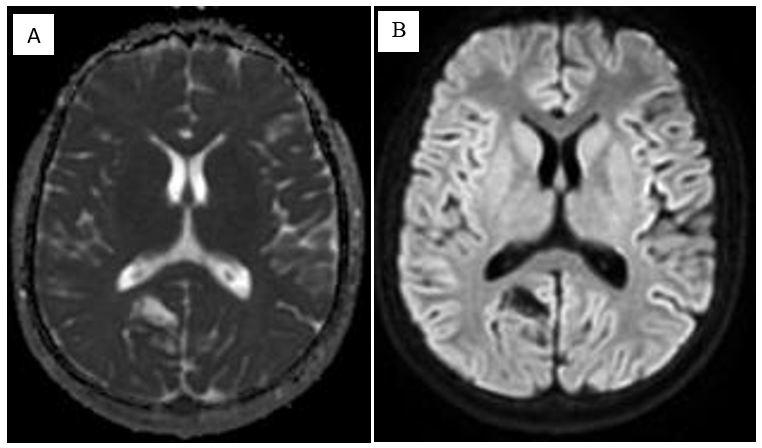

MRI study at admission revealed an ill-defined, irregular, heterogenous, nonenhancing, predominantly cortical-based bubbly appearing cystic lesion involving the right posterior parietal lobe with no perilesional edema – findings that were compatible with a diagnosis of DNET – Type 2 (Figure 1-7).1

Figure 1 (A) Axial and (B) Coronal spin-echo T2-weighted MR images. MRI revealed an ill-defined, cortical-based lesion in the right medial posterior parietal lobe, which appears hyperintense with some thin internal septations. The lesion shows typical "bubbly appearance".

Figure 3 (A) Apparent diffusion coefficient (ADC) map and (B) Diffusion weighted images obtained through the level of lesion show high ADC values inside the lesion and low diffusion on DWI.